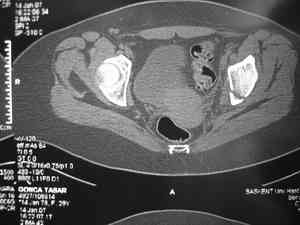

прилагаю пример с такой же давностью травмы, репонировали аппаратом